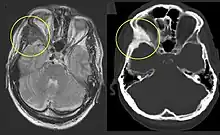

Fibrous dysplasia of the right zygomatic bone (left). Corresponding T2-weighted MRI (left) and CT (right) of the same patient.

Fibrous dysplasia is a mosaic disease that can involve any part or combination of the craniofacial, axillary, and/or appendicular skeleton.[7] The type and severity of the complications therefore depend on the location and extent of the affected skeleton. The clinical spectrum is very broad, ranging from an isolated, asymptomatic monostotic lesion discovered incidentally, to severe disabling disease involving practically the entire skeleton and leading to loss of vision, hearing, and/or mobility.